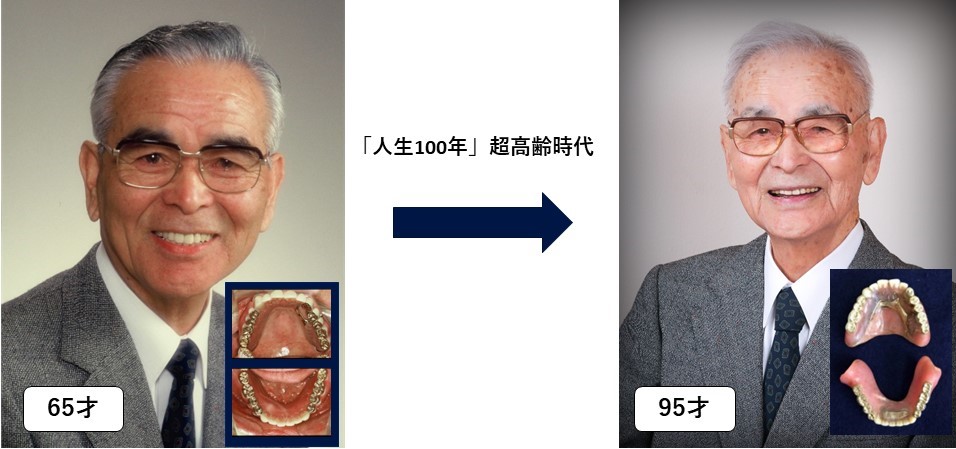

Amazon.co.jp: 義歯に血の通うまで アルプス歯科の総義歯製作。Amazon.co.jp: 義歯に血の通うまで アルプス歯科の総義歯製作。Amazon.co.jp: 義歯に血の通うまで : 中込敏夫, 向井道夫: 本。令和六年度 魚沼産コシヒカリ5キロと新潟県産コシヒカリ5キロ、計10キロ。株式会社 医療情報研究所 | 早くて簡単!総義歯吸着の神技。GPによる複製義歯を利用した総義歯製作 冨田 知孝先生。総義歯づくり すいすいマスター 総義歯患者の「何ともない」を。噛める、痛くない、審美的入れ歯で快適生活 「入れ歯110番。41dgXQG+tOL._BO30,255,255,。医学のあゆみ 289巻5号 MASLD/MASH ─研究と診療の最新情報 5月。総義歯の病理―基礎と臨床から導き出された総義歯製作法。学術04(最終回)「医科歯科介護」連携時代の保険で『噛める総。総義歯の病理―基礎と臨床から導き出された総義歯製作法。サンバレー書房カバーは若干スレあり中身は綺麗です定価20000円神経質な方はご遠慮ください#歯科医師#義歯#歯科技工士